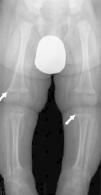

Posteriormente, se comprueba una hipofosfatemia, valores altos de fosfatasa alcalina y de hormona paratiroidea, y bajos de vitamina D compatibles con raquitismo carencial (tabla 1). El ionograma en orina fue normal. La radiografía de tórax y extremidades evidencia signos de raquitismo (fig. 1). Se inicia tratamiento sustitutivo con calcio (a dosis de 70mg/kg/día), calcitriol (a dosis de 100ng/kg/día) y vitamina D (3.000UI/día), y durante las convulsiones se administra gluconato cálcico al 10% (0,5ml/kg en 30min). Presenta progresivamente una mejoría clínico-analítica. El paciente recibió el alta hospitalaria al décimo sexto día de ingreso manteniendo niveles de calcio correctos en controles posteriores.

Caso Clínico 2. Lactante de 7 meses, de origen marroquí y sexo masculino que en las últimas horas realiza 3 episodios de hipertonía generalizada con desviación de la mirada. En los días previos presenta cuadro de dificultad respiratoria orientado como laringitis con irritabilidad marcada. Hijo de padres consanguíneos de origen marroquí, alimentado con lactancia materna habiendo iniciado alimentación complementaria. Desde el nacimiento recibe poca exposición solar. Al ingreso presenta un peso de 8,5kg (p50) y talla de 68cm (p50). En la exploración física presenta irritabilidad y estridor inspiratorio siendo el resto de la exploración normal. La analítica de sangre revela un calcio total e iónico de 5,6mg/dl y 0,61mmol/l respectivamente, con niveles aumentados de fosfato, fosfatasa alcalina y parathormona (tabla 1). El ECG muestra presenta ritmo sinusal con ondas T picudas y intervalo QT corregido discretamente alargado. Se realiza una serie esquelética que detecta alteraciones metafisarias compatibles con raquitismo (fig. 2). Con la orientación diagnóstica de raquitismo carencial se inicia tratamiento sustitutivo (calcio 80mg/kg/día, calcitriol 90ng/kg/día, vitamina D 3.000UI/día y gluconato cálcico 10% de rescate 0,5ml/kg en 30min). El estudio del metabolismo del calcio en la madre es normal. Durante el ingreso presenta buena tolerancia al inicio de la alimentación complementaria con cereales y una corrección favorable de la hipocalcemia. A los 9 días de ingreso recibe alta hospitalaria, realizándose seguimiento en consultas externas.